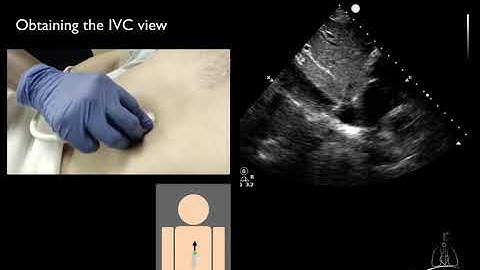

How to: Echocardiography - Subxiphoid View